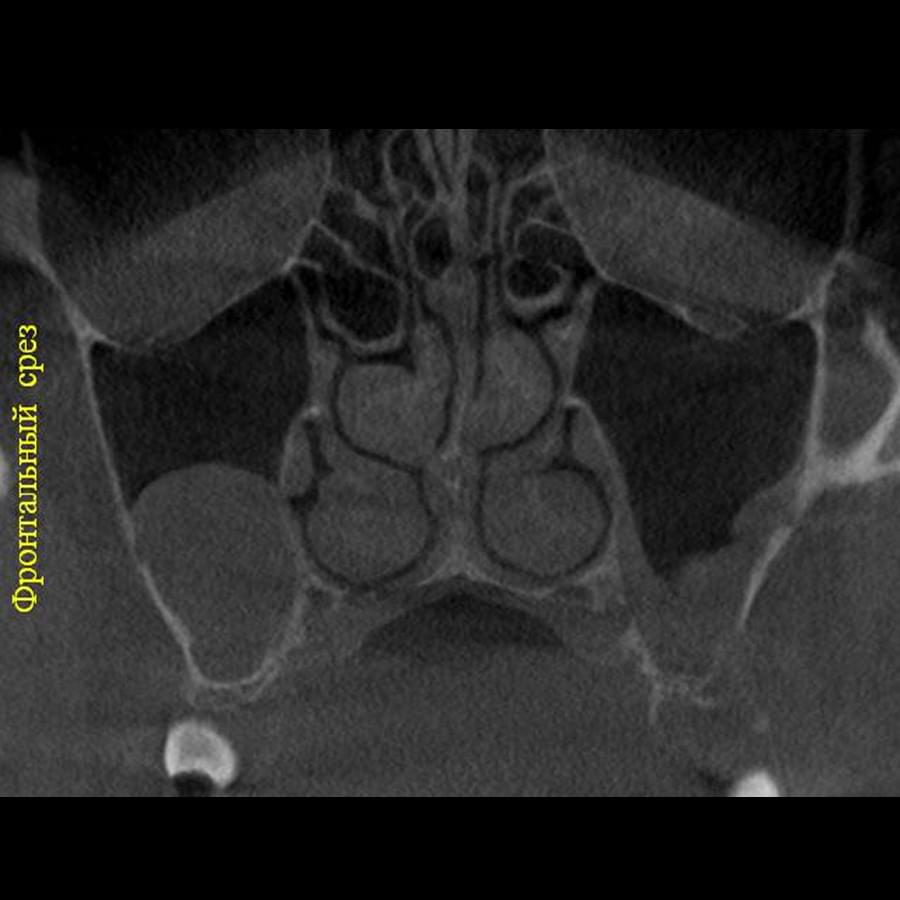

3D цефалометричний аналіз є сучасною технологією, яка дозволяє отримувати точніші,

комплексніші та надійніші дані про зубну та скелетну структуру. Ця технологія може стати

великим кроком в перед для ортодонтів, які хочуть забезпечити найкраще можливе лікування

своїх пацієнтів.

Надійність: 3D цефалометричний аналіз дозволяє отримувати надійніші результати, оскільки

виключає можливість помилок, пов'язаних зі спотворенням або перекриттям зображень.